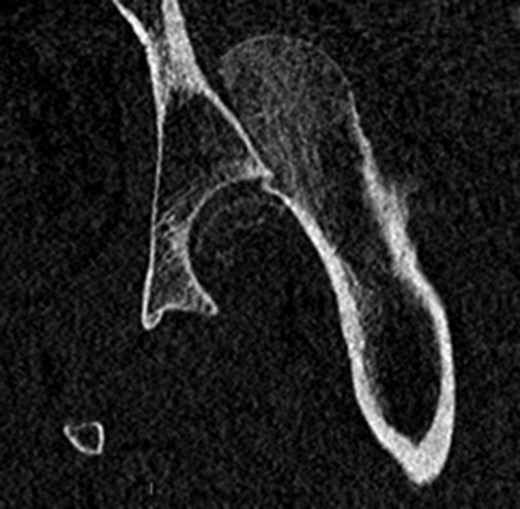

In addition to the bony injury, labral detachment and tearing were noted (later repaired with suture anchors). The femoral head was comminuted and had areas of missing articular cartilage especially posteriorly and superiorly with a 1 × 1 cm2 area of full thickness cartilage loss (Fig. 4). The weight-bearing zone was relatively unaffected. The ligamentum teres had to be released to allow fracture reduction and fixation with four headless compression screws (Fig. 5). A good fixation was achieved. Microfracture was performed on the articular cartilage defect. The femoral head, fracture fragment and microfracture site were bleeding and appeared viable.

Intraoperative view of the femoral head with temporary fixation with wires.